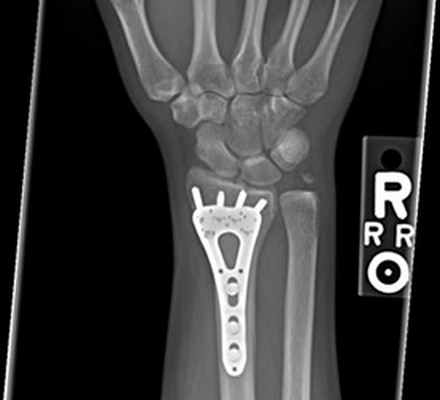

При переломах диафиза и метафиза обеих костей или изолированных переломах лучевой и локтевой костей остеосинтез производят прямыми узкими, желобоватыми пластинами.

Принципы экстракортикального остеосинтеза костей предплечья.

Остеосинтез при переломах дистального отдела лучевой кости производят редко, как правило, при неудаче консервативного лечения. Для остеосинтеза применяют малую Т-образную пластину (Рис. 140).

Остеосинтез лучевой кости в дистальном отделе